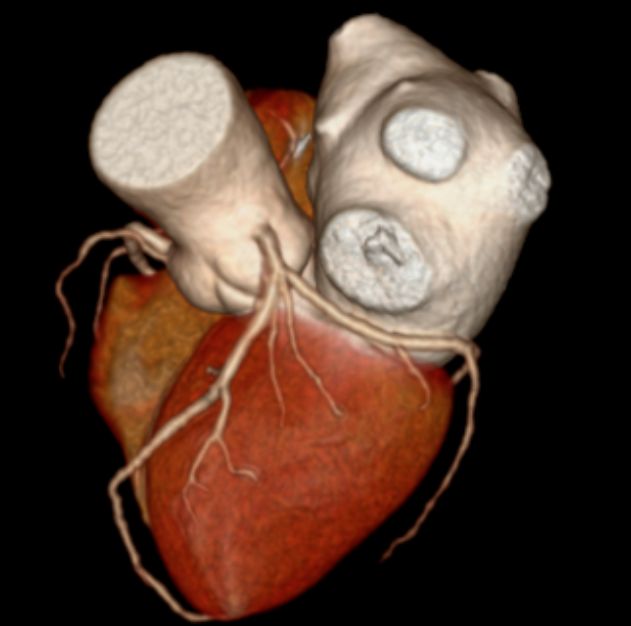

CT表现:冠状动脉粥样硬化,左冠状动脉前降支近端中度狭窄,左冠状动脉前降支心肌桥形成。

冠状动脉CTA已成为筛查和诊断冠状动脉疾病的无创性“金标准”之一。它通过静脉注射对比剂,利用CT快速多层扫描和三维重建技术,直观展示冠状动脉的走行、管腔狭窄程度、斑块性质(如钙化斑块或软斑块)以及血管壁的情况。对于像张老先生这样的病例,CTA不仅能精准测量狭窄百分比,还能识别心肌桥这一解剖变异,评估其与狭窄的相互影响,为临床制定治疗方案(是药物保守治疗,还是需要介入支架或外科搭桥)提供了至关重要的参考。报告中提到的宽体探测器技术,代表了当前CT发展的前沿方向,特别适用于心率快、心律不齐、不能配合屏气或身体虚弱的患者,极大地拓宽了心脏CT检查的适用人群和诊断成功率。